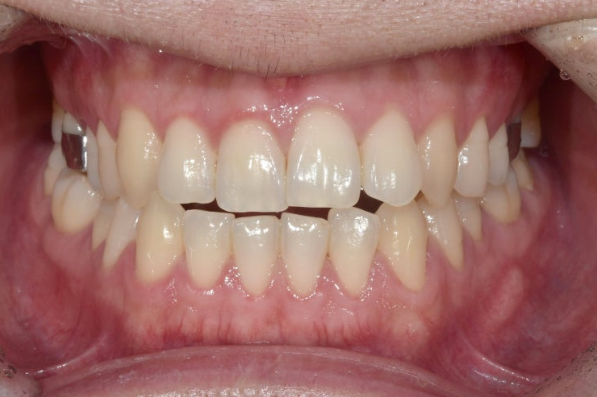

This patient visited us in December 2022 to correct anterior crossbite and open bite.

The blue arrow indicates that the molar bites in reverse.

This is called a crossbite.

Because the lower arch is wider than the upper arch, this is a crossbite.

In addition, due to the underbite, crossbite is also seen in the canines and front teeth.

A mandibular asymmetry with the lower jaw shifted to the right is also visible, along with an open bite where the upper and lower teeth do not meet.